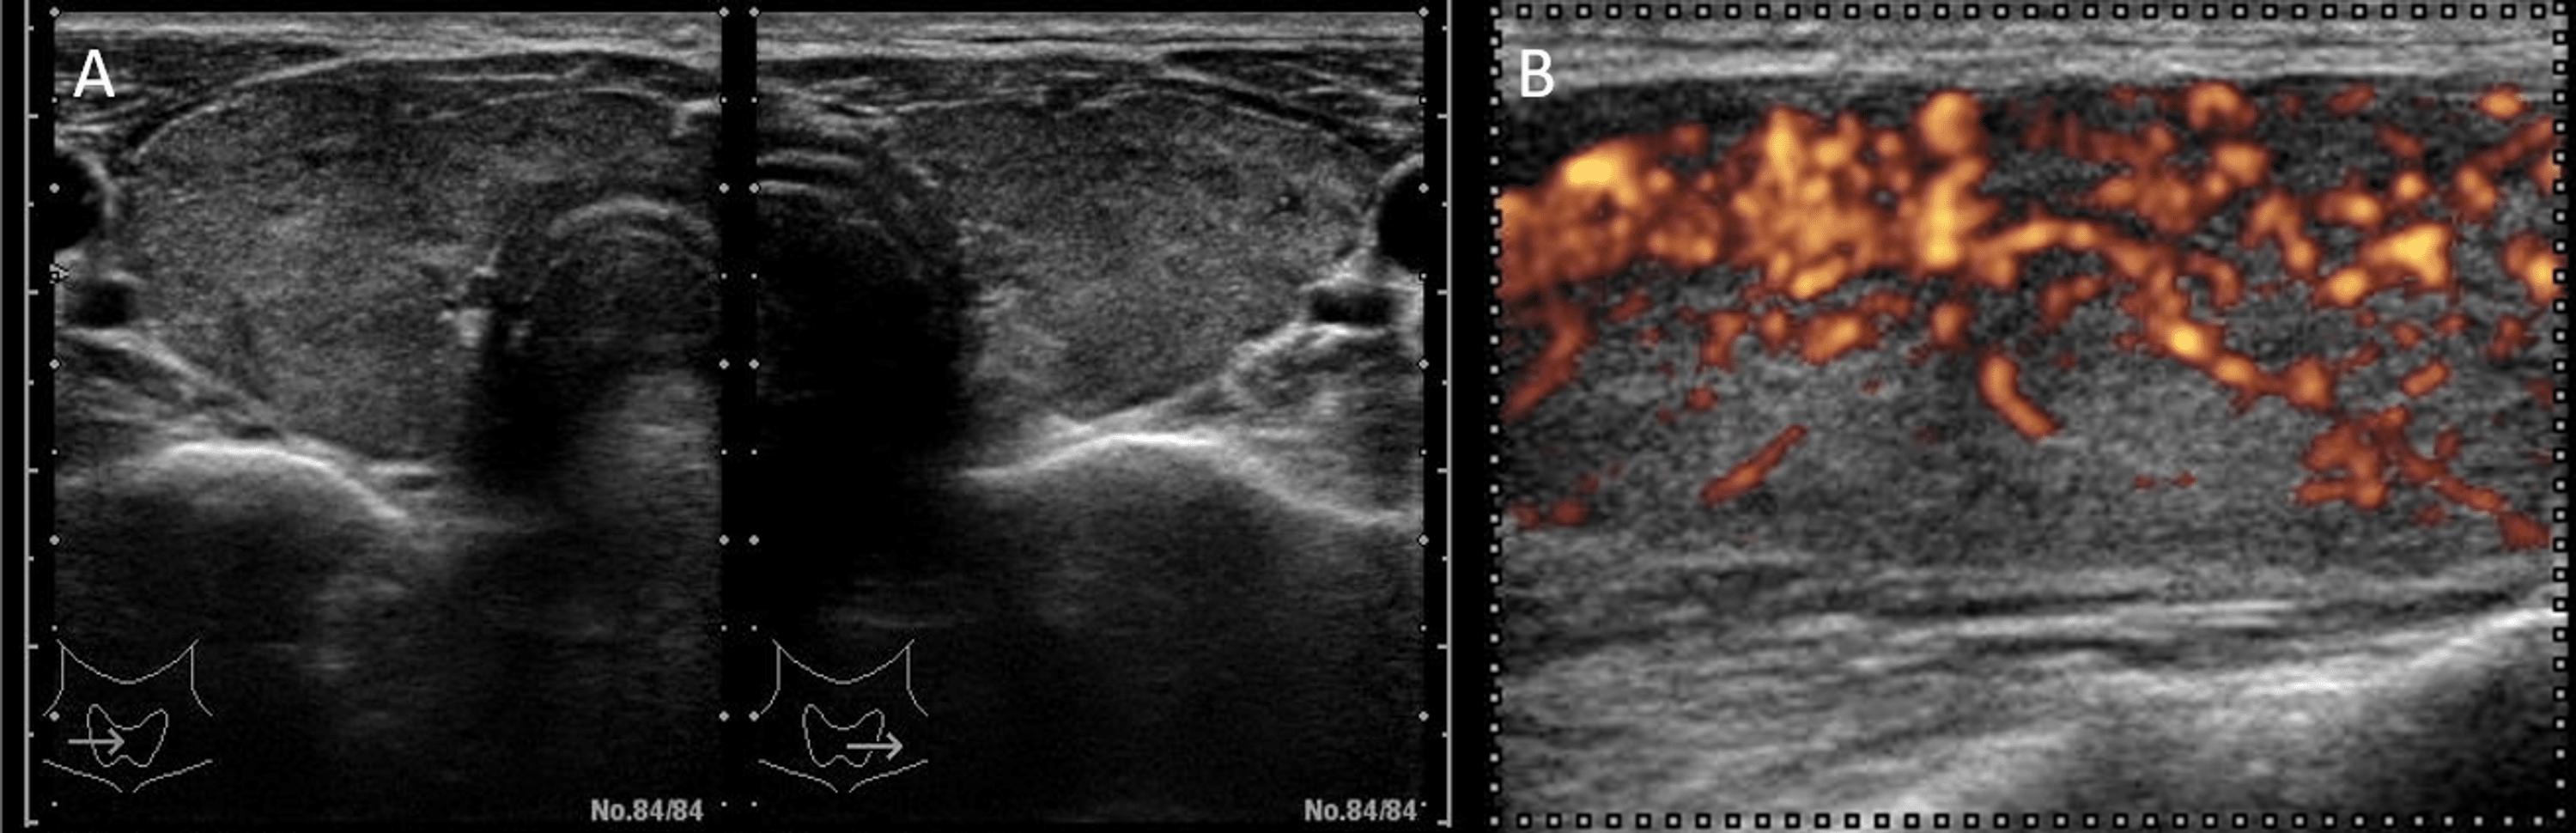

Figure 1 from Thymic hyperplasia in patients with Graves' disease Thymic Hyperplasia Graves Thymic hyperplasia in graves' disease is related to excess thyroid hormones and thyrotropin receptor antibody. Thymic hyperplasia is commonly associated with graves' disease, but it is not emphasized in major endocrinology texts and must be recognized by. As a common reason of hyperthyroidism, graves’ disease may be associated with other autoimmune disorders [1], among which thymic hyperplasia was. It is. Thymic Hyperplasia Graves.